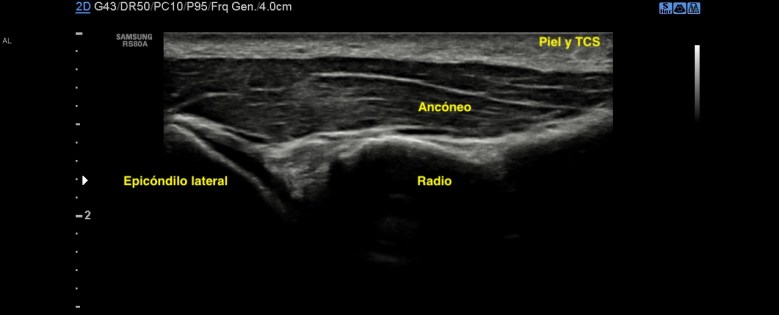

Ecográficamente es bastante normal, no es difícil de localizar si sabes su disposición anatómica, pero la verdad, no se suele mirar. Yo te lo enseño para que lo veas:

Hipoecogénico, de disposición oblicua a l ahora de colocar el traductor, profundo, alargado, cercano a la articulación, como protegiéndola.